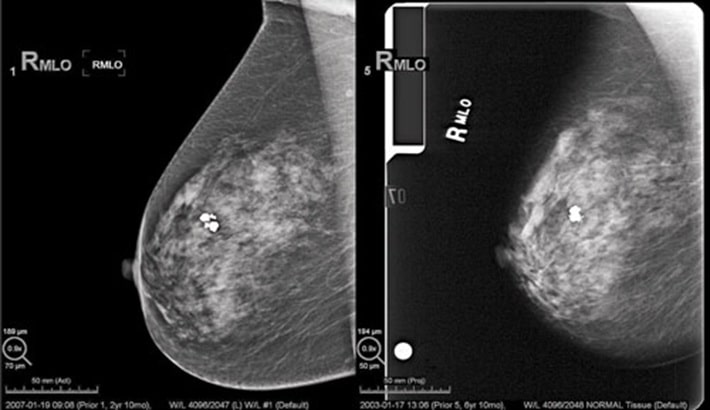

بیوپسی یکی از حساسترین و قطعیترین روشهای تشخیص سرطان سینه است. زمانی که در معاینات فیزیکی یا در تصویربرداریهایی مثل ماموگرافی و سونوگرافی، تغییرات مشکوک مشاهده شود، پزشک برای اطمینان از ماهیت بافت، نمونهبرداری را توصیه میکند. اهمیت این روش در این است که برخلاف تصویربرداری که صرفاً ظاهر و ساختار بافت را نشان میدهد؛ بیوپسی مستقیماً سلولها را بررسی میکند و وجود سلولهای سرطانی یا پیشسرطانی را مشخص مینماید.

علائم سرطان سینه در زنان که منجر به انجام بیوپسی میشود؛ شامل وجود توده سخت، تغییرات پوستی غیرعادی، ترشحات غیرطبیعی یا تغییر شکل نوک سینه است. در این شرایط، تشخیص دقیق نوع سلول سرطانی، درجه بدخیمی و حتی گیرندههای هورمونی، تنها از طریق بررسی بافت زیر میکروسکوپ امکانپذیر است.

علائم سرطان سینه در زنان میتواند شبیه بیماریهای خوشخیم سینه مثل فیبروآدنوم یا کیست باشد. تصویربرداری به تنهایی قادر به تشخیص قطعی نوع ضایعه نیست. بیوپسی این امکان را فراهم میکند که پاتولوژیست سلولها را بررسی کند؛ همچنین نوع تومور، سرعت رشد و حساسیت آن به هورمونها یا داروها را مشخص کند.

بهعنوان مثال، دو توده با ظاهر مشابه در ماموگرافی میتوانند نتایج کاملاً متفاوتی داشته باشند؛ یکی خوشخیم و دیگری بدخیم. تنها بیوپسی میتواند این تفاوت حیاتی را مشخص کند و مسیر درمان را تعیین نماید.